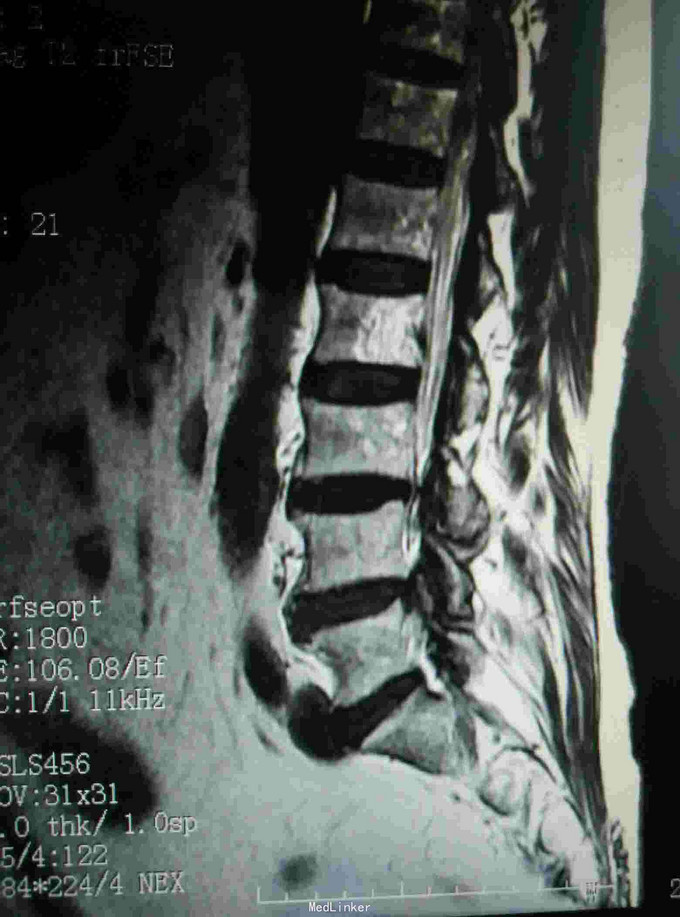

腰痛伴左下肢疼痛不适半月 患者无明显诱因出现腰痛,伴有沿左大腿根部后侧至外踝的疼痛,行走加重,休息可有缓解,期间未做特殊处理,外院核磁提示椎管内肿物,为求进一步诊治入我院。

查体:脊柱生理弯曲存在,腰骶部棘突及椎旁压痛,双下肢肌力IV级,双上肢肌力正常,下肢自主活动无异常,直腿抬高实验阴性,余检查无明显异常。 辅查:核磁提示L3-4椎管内肿物,L4-5椎间盘突出

诊断:椎管内良性肿瘤,腰椎间盘突出 治疗:椎管内肿物切除+腰椎内固定